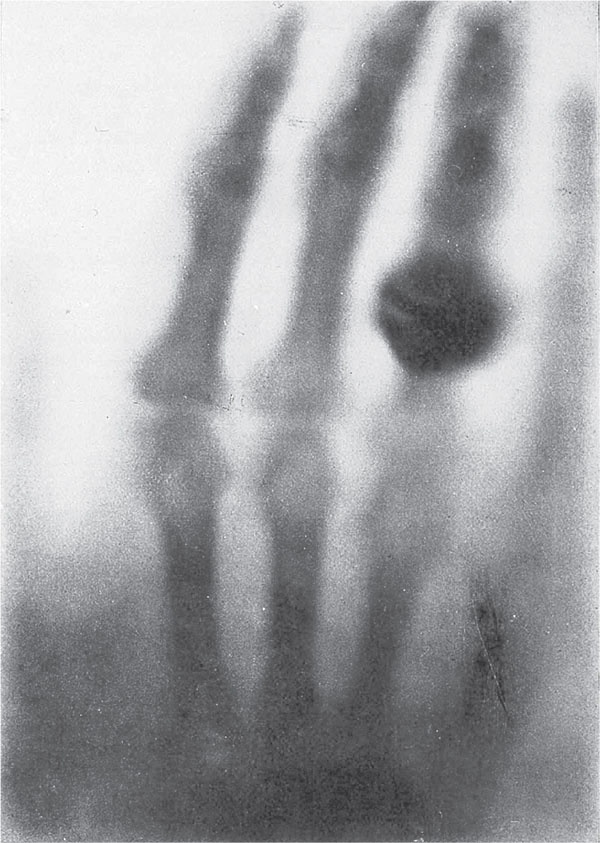

На одном из первых рентгеновских снимков мы видим кости и замечательное кольцо Берты Рентген, жены Вильгельма Рентгена. Вильгельм, опасавшийся, что сошел с ума, успокоился, когда супруга тоже увидела свои кости на покрытой барием пластинке. Она, будучи не такой отважной, приняла этот снимок за предзнаменование смерти